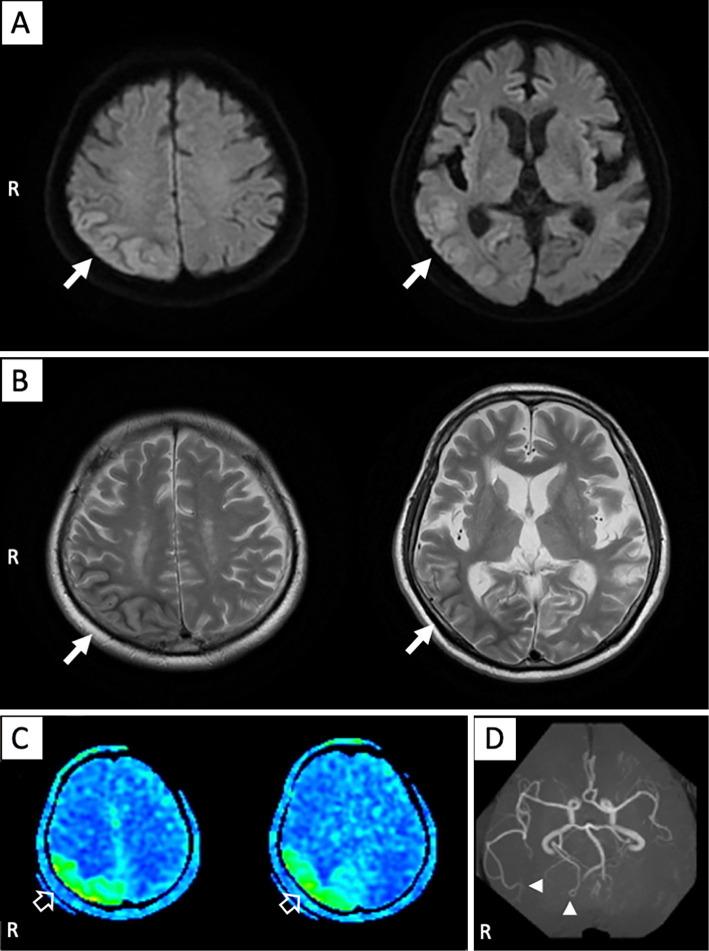

A 68-year-old man was admitted to our department because of left incomplete homonymous hemianopia accompanied by hyperglycemia. Both T2-weighted and diffusion-weighted imaging revealed a low signal intensity along the subcortex and high signal intensity along the cortex on the right parietal and occipital lobes. Furthermore, arterial spin labeling and single-photon emission computed tomography showed hyperperfusion at the right parieto-occipital lobe. However, the electroencephalography result was normal. Hyperperfusion improved after controlling the blood glucose levels; nevertheless, homonymous hemianopia remained. We suspect that the irreversible brain damage was attributable to hyperperfusion associated with long-term hyperglycemia.

一位 68 岁男性因左不完全面盲伴高血糖症被收入我科。T2 加权像和弥散加权成像显示右侧顶叶和枕叶皮质及皮质下均呈低信号,而呈高信号。此外,动脉自旋标记和单光子发射计算机断层扫描显示右侧顶枕叶高灌注。然而,脑电图结果正常。血糖控制后高灌注改善,但仍存在同向偏盲。我们怀疑与长期高血糖相关的高灌注导致了不可逆转的脑损伤。